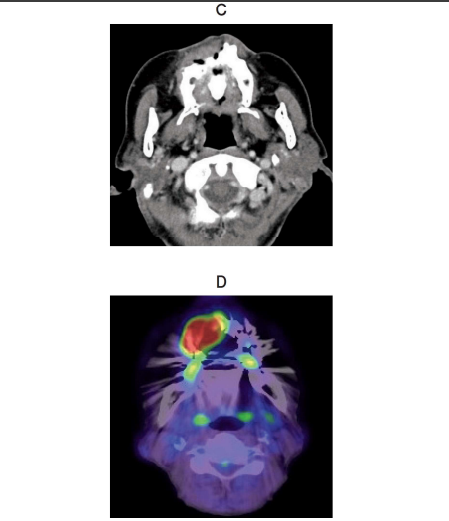

80 歳の女性。上顎右側歯肉の腫脹を主訴として来院した。 2 か月前から徐々に増大してきたという。15 年前に脳梗塞を発症し、10 年前から関節リウマチと骨粗鬆症で投薬を受けている。初診時の口腔内写真(別冊No. 7A)、エックス線画像(別冊No. 7B)、造影 CT(別冊No. 7C)、FDG-PET/CT(別冊No. 7D)及び生検時のH-E 染色病理組織像(別冊No. 7E)を別に示す。

病変の誘因と考えられるのはどれか。 1 つ選べ。

解答:b

解説:

関節リウマチの薬といえば、メトトレキサート。

メトトレキサートの長期投与により、メトトレキサート関連リンパ増殖性疾患が引き起こされる。

Eの病理組織像を見ると、リンパ球の増殖、異型リンパ球がみられる。